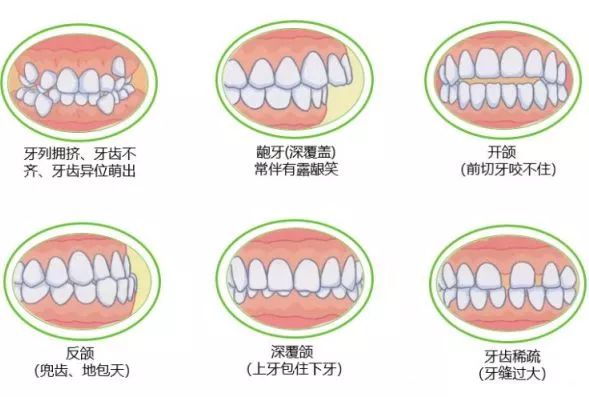

出現咗錯頜畸形(牙齒唔齊)嘅症狀...

越嚟越多啲細路嘅牙齒開始唔係整齊“好似玩套牌咁”,

隨住食物愈嚟愈細緻,大大減少咗食嘢時嘅咀嚼動作對嚼肌生長嘅刺激,導致頜骨唔能夠正常生長。一旦脣下骨發育不全,牙齒生長空間就唔夠,就註定有牙要見縫插針、壞野生出嚟。

牙齒唔齊有哪些危害?